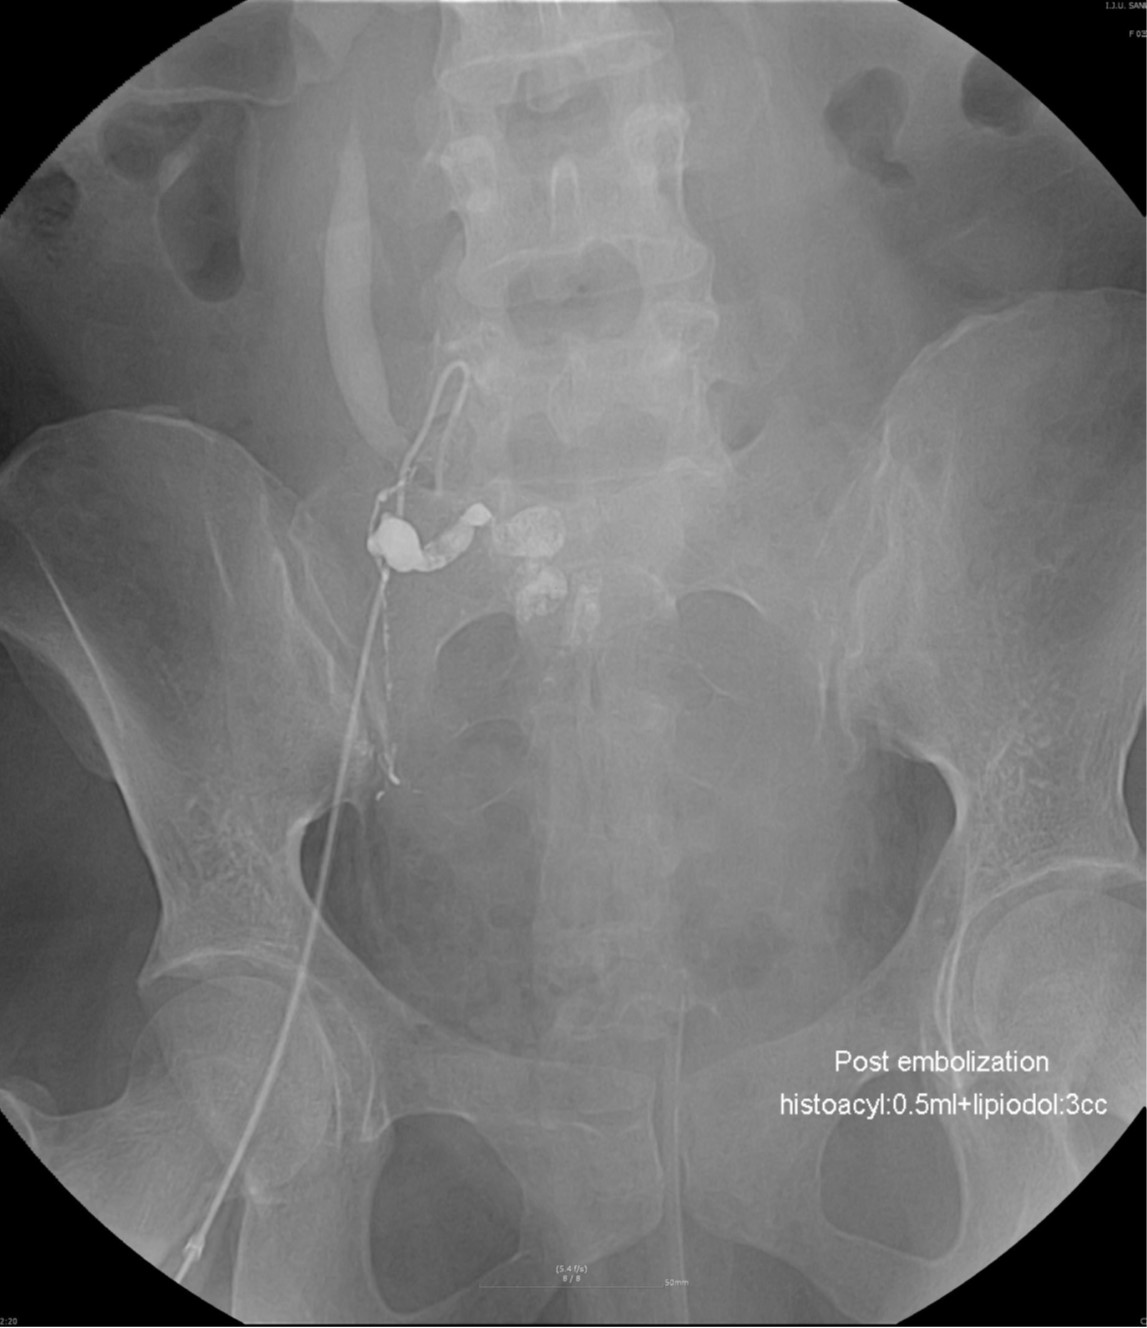

Fig. 4.

The pelvic radiograph shows tubular and linear radiopaque casts of NBCA/lipiodol mixture within the right uterine artery, pseudoaneurysm, and extravasation area.